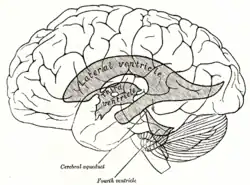

Le système ventriculaire est un ensemble de cavités situées à l'intérieur du cerveau en continuité avec le canal de l'épendyme (ou canal central) de la moelle spinale[1]. Il participe à la sécrétion et à la circulation du liquide cérébrospinal (ou céphalorachidien) où baigne le système nerveux central. Il est constitué principalement de quatre ventricules :

- deux ventricules latéraux, droit (situé dans l'hémisphère cérébral droit) et gauche (situé dans l'hémisphère cérébral gauche) : en forme de fer à cheval, ils sont constitués de trois cornes – frontale (antérieure), occipitale (postérieure) et temporale (inférieure) – se réunissant au niveau de l'atrium (ou carrefour) situé derrière le thalamus[2] ;

- le troisième ventricule (situé dans le diencéphale) : cavité étroite entre les thalamus, elle présente trois étages, thalamique, sous-thalamique et infundibulo-tubérien[3] ;

- le quatrième ventricule (situé dans le rhombencéphale) : en forme de losange, aplati dans le sens antéro-postérieur[4].

Les ventricules communiquent entre eux :

- entre les ventricules latéraux et le troisième ventricule : les foramens interventriculaires (ou trous de Monro) ;

- entre le troisième et le quatrième ventricule : l'aqueduc du mésencéphale (anciennement aqueduc de Sylvius).